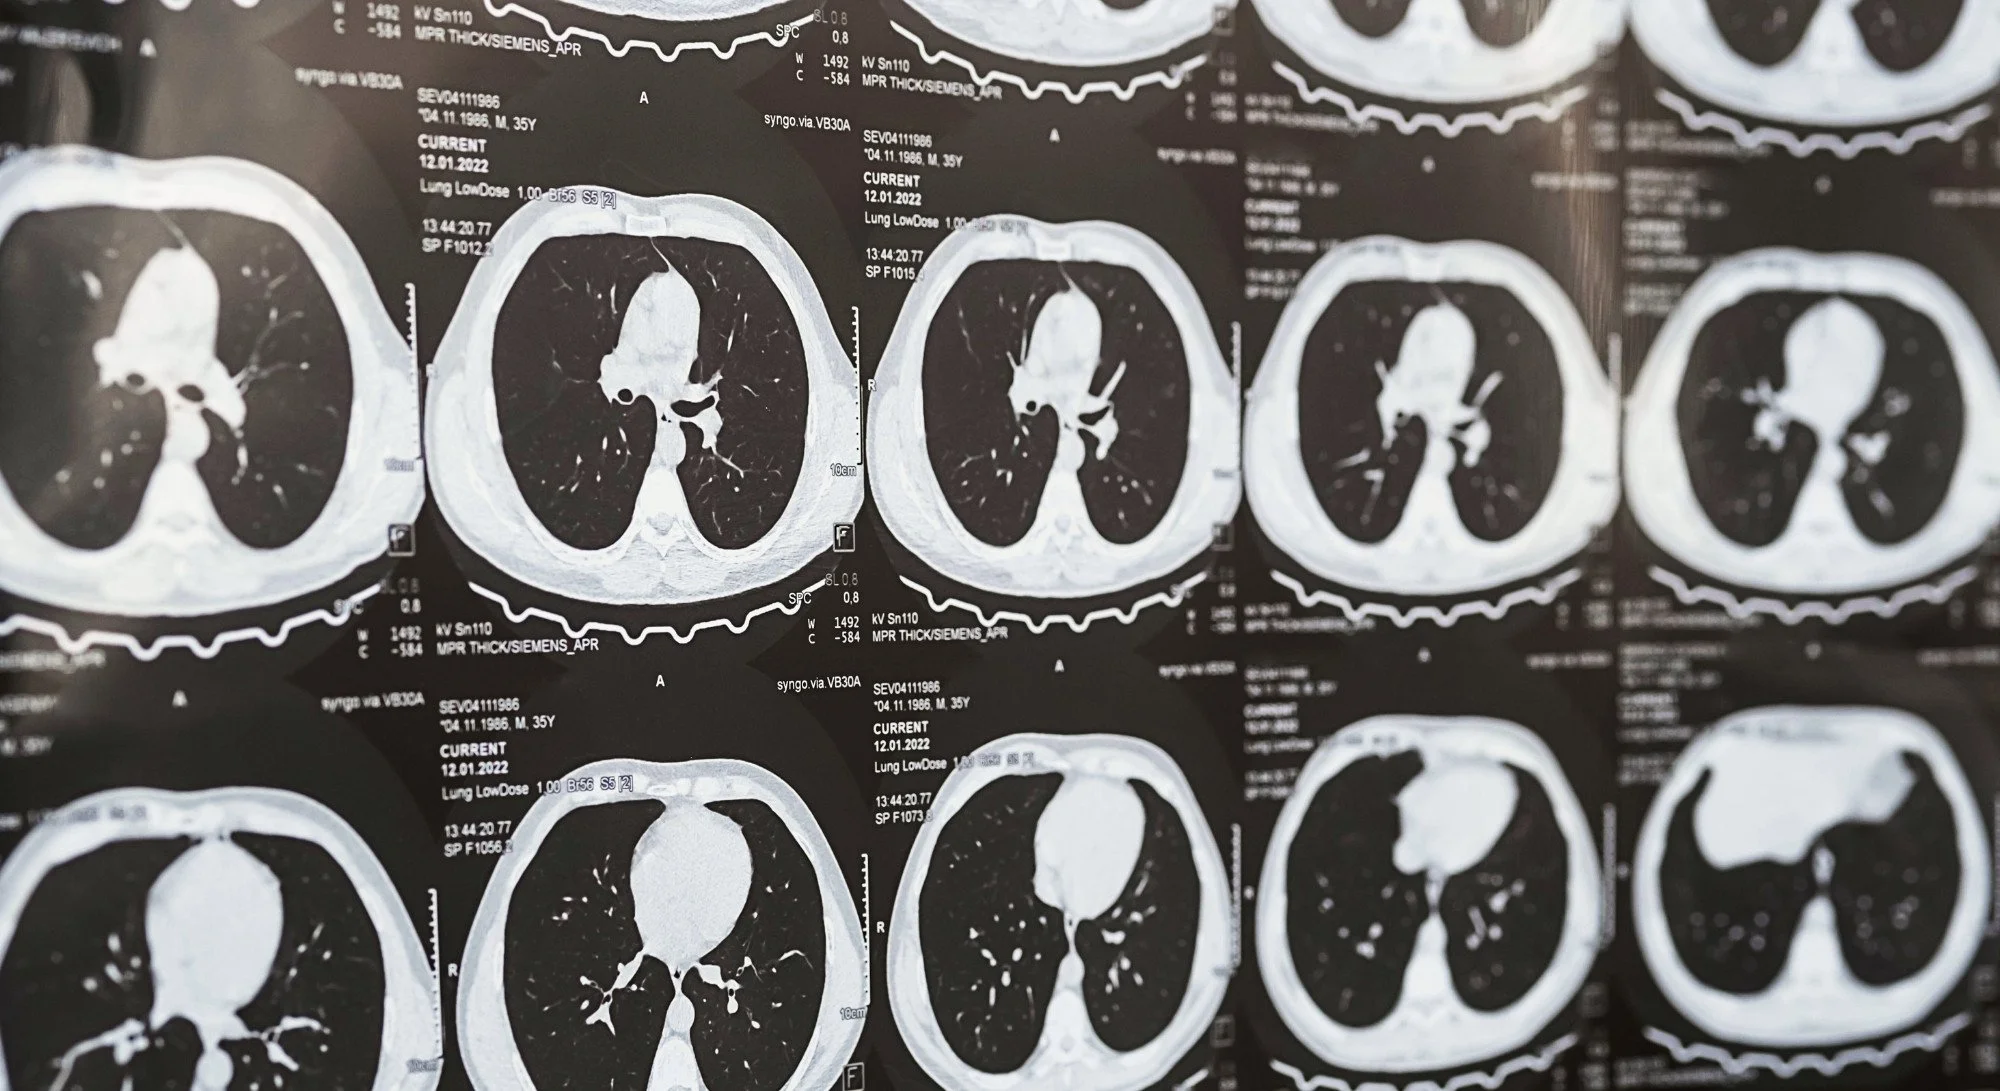

Black and white cross-section images of a pair of lungs

A CT scan (short for “computed tomography”) is a type of medical imaging test. Think of it like an advanced X-ray that takes detailed pictures of the inside of your body. While a normal X-ray gives a flat image, a CT scan takes many pictures from different angles and puts them together to create a 3D image. When it's focused on your chest, it gives doctors a clear view of your lungs, heart, blood vessels, airways, and even bones.